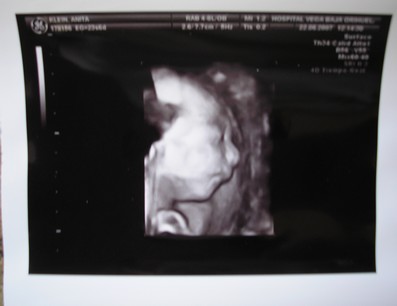

A kisbabád meg nagyon szép, nagyon jó kép lett róla. Olyan jó, hogy kislány lesz, nagyon sok szép kisasszonynév van, bő a választék. Bezzeg fiúból... ezért nincs is még lekonkretizálva mindig a mienké, de nem lesz nevesincs királyfi, az tuti